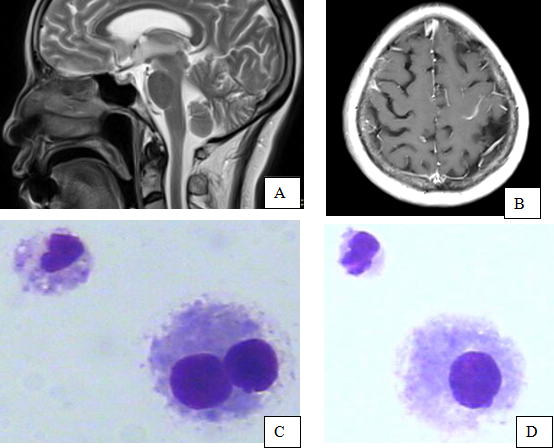

> 4月27日头颅CT示:小脑、左额顶局部脑沟变浅,呈明显增强,符合结核性脑膜炎改变,未见明显肿物影(见图A、B)。

> 5月8日转入某结核病院,T 36.5℃,急性病容,颈抵抗4横指,电解质:K 3.81mmol/L,Na 129 mmol/L,Cl 91.4mmol/L。CRP 20.8 mg/L。头颅核磁仍报告为脑膜炎,根据病史、症状、查体、辅助检查等,经全院会诊支持结核性脑膜炎诊断,暂时给予抗感染、调节免疫力、HRZEV抗痨、脱水降颅压治疗及对症处理。行腰椎穿刺术数次,CSF常规白细胞数:(1~3) ×106/L,CSF生化蛋白(2~3.5)g/L,葡萄糖(1.7~2.3) mmol/L、氯化物(98~105)mmol/L,脑膜刺激症状仍无明显改善。脑脊液细胞学发现数个异型组织细胞(如图C、D),高度怀疑脑膜癌,肿瘤全项:CEA8.02 ng/ml,CA153 45.69 U/ml,铁蛋白786ng/ml,均明显高于正常,故肺癌脑膜转移不除外,患者及家属要求出院,愿承担一切后果,自动出院。

脑膜癌多数为颅外恶性肿瘤转移而来,也可由神经系统的原发肿瘤播散而致或原发于脑膜。主要以恶心、呕吐起病,因脑膜癌临床表现不典型,且头痛等症状常发生于原发病灶出现症状之前,极易误诊。因癌细胞沿脑膜弥漫性转移,癌细胞和软脑膜密度一样,无明显肿块,早期头颅CT或MRI检查无异常表现。此患者可见脑膜强化,所以三家医院放射科皆报告为脑膜炎。目前任何检查均不能代替脑脊液细胞学检查,镜下找到癌细胞是诊断脑膜癌病的金标准,脑脊液细胞学诊断脑膜癌敏感性为75%-90%,特异性为100%。